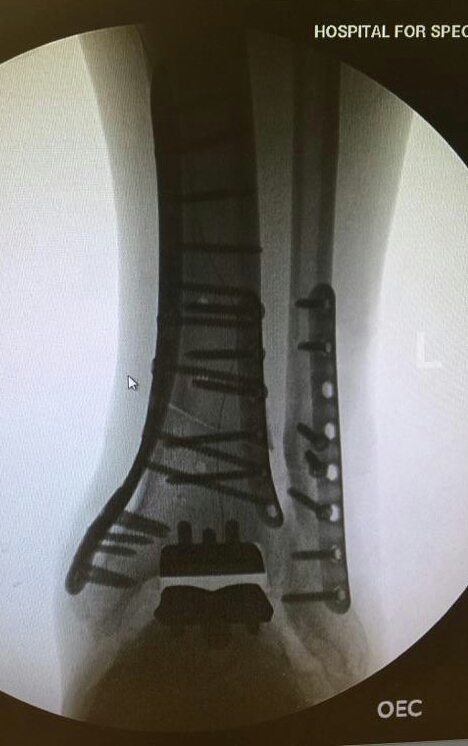

In January 2016, my life dramatically changed for the better thanks to the best HSS surgical team assembled to correct a severely painful, arthritic ankle and misaligned lower leg. Dr. Demetracopoulos is a highly skilled surgeon who performed a total ankle replacement (TAR) on my left ankle. In conjunction with the TAR, I was also the recipient of a much needed osteotomy to align my lower leg to the ankle implant so that my foot would point forward again and perfectly contact the ground in a level position to improve my gait.

Dr. Fragomen was a major contributor to these surgical procedures and I cannot thank him enough as well for helping. Just 3-1/2 years earlier in 2012, Dr. Fragomen performed a procedure on this same troubled ankle called arthrodiastasis in an attempt to allow my joint relief from bone-on-bone pain with distraction using external fixation for over 5 months. Unfortunately, arthrodiastasis only provided relatively short-term relief and some pain reduction. After a couple of years, my left ankle would again become painful and need a correction in the form of total reconstruction if I ever wanted long-term relief from pain and a return to a normal walking motion without a limp. Dr. Fragomen referred me to Dr. Demetracopoulos, the TAR specialist extraordinaire! Dr. "D" (easier to say) gave me my second opinion at HSS, since the first TAR surgeon with whom I consulted recommended two separate surgeries over the course of a year - first, to correct the lower leg alignment, then, after that healed, to do the ankle replacement. But then I visited Dr. D - he was like Superman to the rescue when he stated his confidence in accomplishing the same positive results performing both corrective procedures in ONE surgery! With one surgery I would only be subjected to one recovery period to heal from both procedures. I am blessed to have been introduced to such a miracle worker!